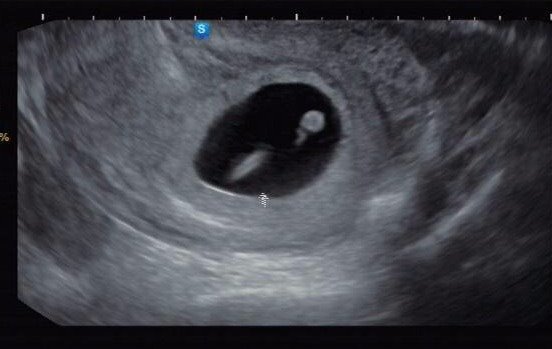

임신 7주차 총총이.

드디어 3주 만에 초음파로 만난 총총이는 약 1.22cm크기로 자라 있었다. 어른 손가락 한 마디도 되지 않는 작은 크기였다.

그리고 그 작은 몸 — 이라고 하기에도 너무 작은 무엇 — 에서 심장이 뛰고 있었다!

인간의 심박이라기에는 조금 빠른 그 쿵쾅거림을 듣고 있는데, 총총이의 심장에서 나는 소리라는 게 실감이 안 났다. 처음 겪는 이 모든 일들이 너무나도 비현실적이었다.